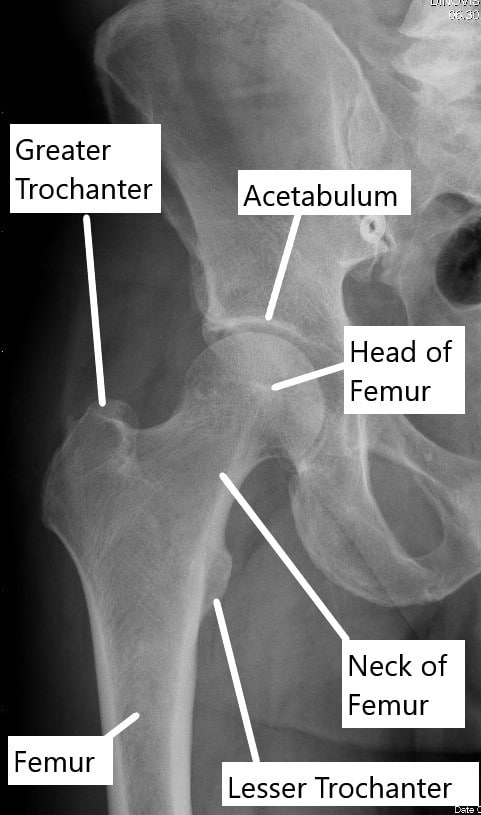

Diagnosis of Bone and Joint Disorders: Resnick, Donald。Diagnosis of Bone and Joint Disorders: Resnick, Donald。Diagnosis of Bone and Joint Disorders: Resnick, Donald。RN出品。Arthritis and Rheum Treatment | Rheumatologist Near Me。今となっては医学書だと思います。詳細は写真をご確認ください。よろしくお願いします。Metabolic Bone Disorder Treatment。Amazon.com: Diagnosis of Bone and Joint Disorders。Paget disease of bone: Video, Causes, & Meaning | Osmosis。A Rare Case of Adolescent Joint Pain in the ED EMRA。寝付けが難しい本かなと感じております。51x8RAhSV1L.jpg。Diagnosing bone disease (Chapter 1) - Pathology of Bone and。綺麗な状態だと思います。Transient-Osteoporosis-of-the-。Diagnosing bone disease (Chapter 1) - Pathology of Bone and。